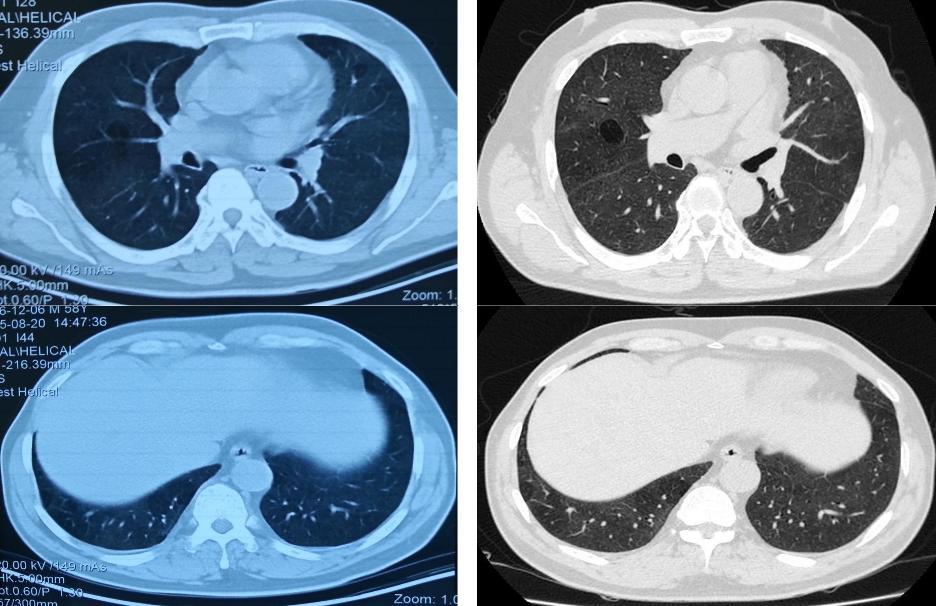

从影像学可以看到,有一些网格索条影,小叶中心型结节,很多气体分布不均,像马赛克征的情况。

胸部CT:不规则索条影、网格、结节(小叶中心)、磨玻璃;肺结构改变更明显,支气管扩张,蜂窝肺;肺皱缩(上叶)下叶代偿性肺气肿,但是无钙化和空洞;马赛克(主要见于亚急性/慢性);支气管血管束增重。

这是一位73岁男性的胸部CT,1991年始咳嗽,CT诊断ILD。激素治疗减轻,2008年活动气短。养鸽子10年×90只,2000年脱离,吸烟3年×2-3支/天,戒烟48年。胸膜下肺 底 分布不是其特点。